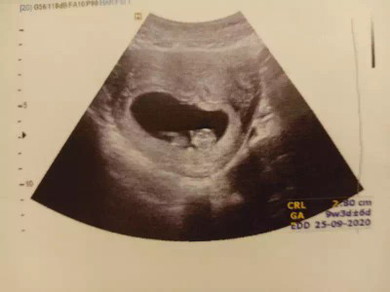

ตอนนี้ท้องได้สองเดือนกว่าๆค่ะ แต่ปวดหลังมากเหมือนคนใกล้คลอด มีอาการฉี่ไม่ค่อยออกเวลาปวดฉี่มากๆด้วยค่ะ และฉี่บ่อยมากกก นอนได้แป๊บๆก็ต้องลุกมาฉี่ตลอด แล้วก็หลับยากอีกทีนี้ ตอนตั้งท้องคนแรกไม่เคยเป็นอะไรเลย..อาการแบบนี้ปกติมั้ยคะ ?? มีบ้านไหนเป็นเหมือนเราบ้าง??